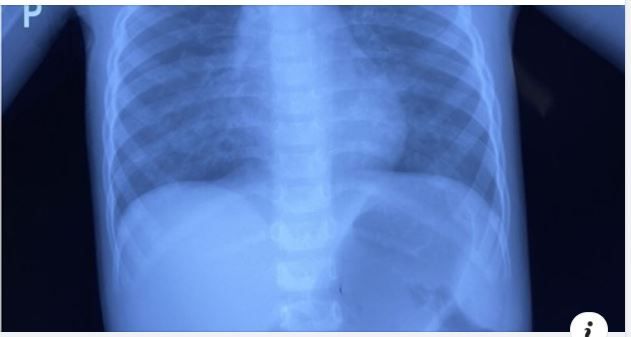

Bé gái 8 tuổi bị răng sữa rơi vào phổi, chiếc răng cắm sâu vào thành phế quản khi tự nhổ răng tại nhà!!Video cảnh giác này, TS BS Trịnh Hồng Nhiên, Trưởng khoa Hô Hấp Bệnh Viện Nhi Đồng Thành Phố sẽ...